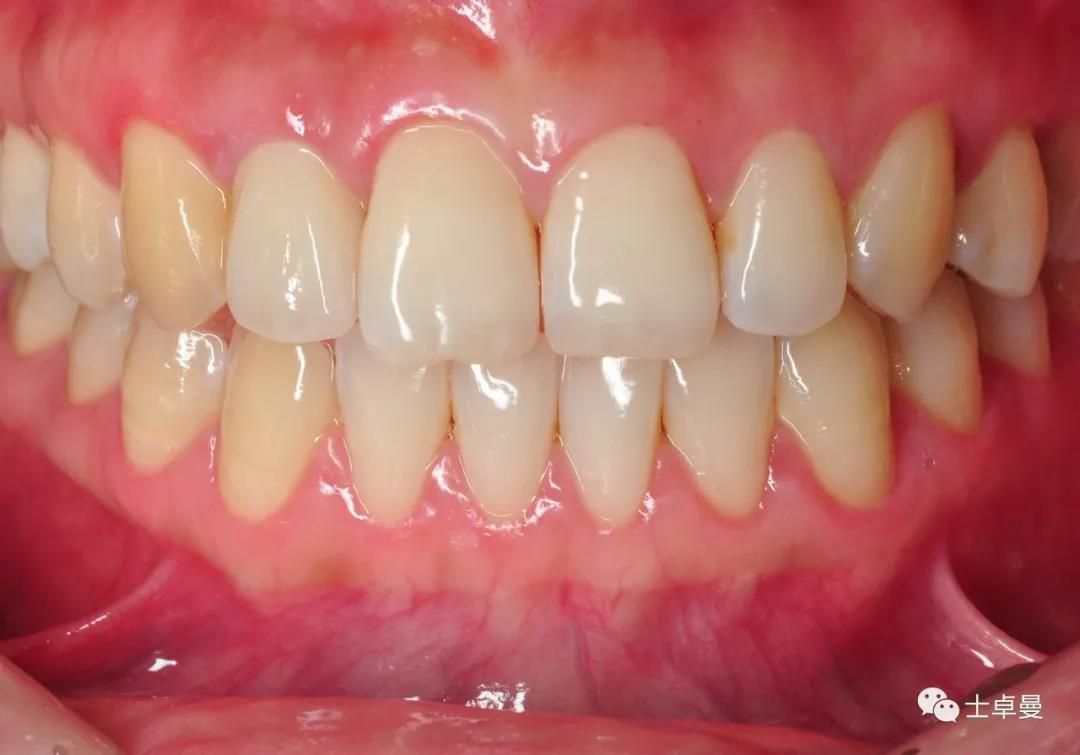

完成修复一年后复查

修复后3年复查

患者微笑照

术后三年的CBCT

不同时期CBCT截图